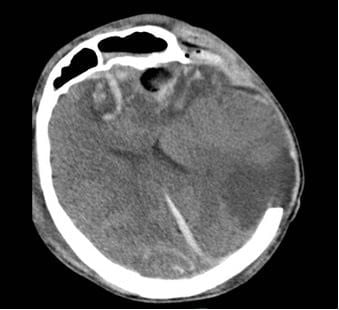

Phim CT não của 2 bệnh nhân

Tại Bệnh viện Nhân dân 115, bệnh nhân G.A nhập viện trong tình trạng hôn mê sâu, phải thở máy nội khí quản. Kết quả chụp CT sọ não cho thấy dập não xuất huyết rải rác nhiều vị trí, phù não lan tỏa nặng, tiên lượng rất dè dặt, nguy cơ tử vong cao. Bệnh nhân được điều trị tích cực tại Đơn vị Hồi sức ngoại khoa, Khoa Gây mê Hồi sức với sự theo dõi sát sao của ê-kíp chuyên môn.

Người mẹ, bà G.N. cũng trong tình trạng rối loạn tri giác, dập não thái dương lượng lớn. Sau hội chẩn kỹ lưỡng, các bác sĩ quyết định lựa chọn phương pháp điều trị bảo tồn nhằm hạn chế tối đa tổn thương thứ phát. Hướng điều trị này cho thấy hiệu quả rõ rệt khi người bệnh dần tỉnh táo, cải thiện khả năng giao tiếp và chức năng ngôn ngữ. Sau 10 ngày điều trị tại Khoa Ngoại thần kinh, bà G.N. hồi phục tốt và được xuất viện.